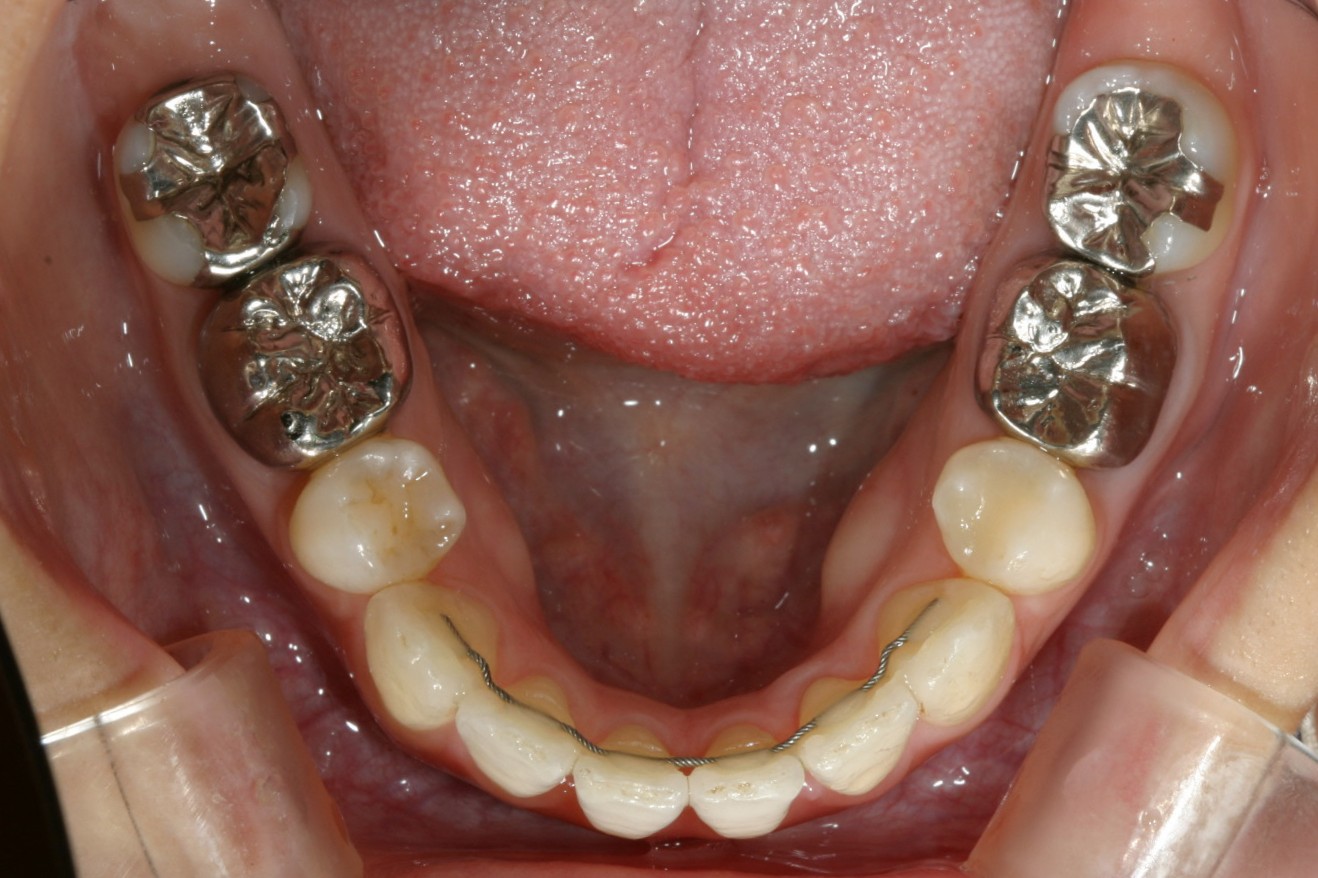

下顎も叢生が出てきています。

下顎も叢生を改善しました。

特に上顎のアーチが狭くなり先が尖って、それに合わせて下顎も叢生が再発していました。